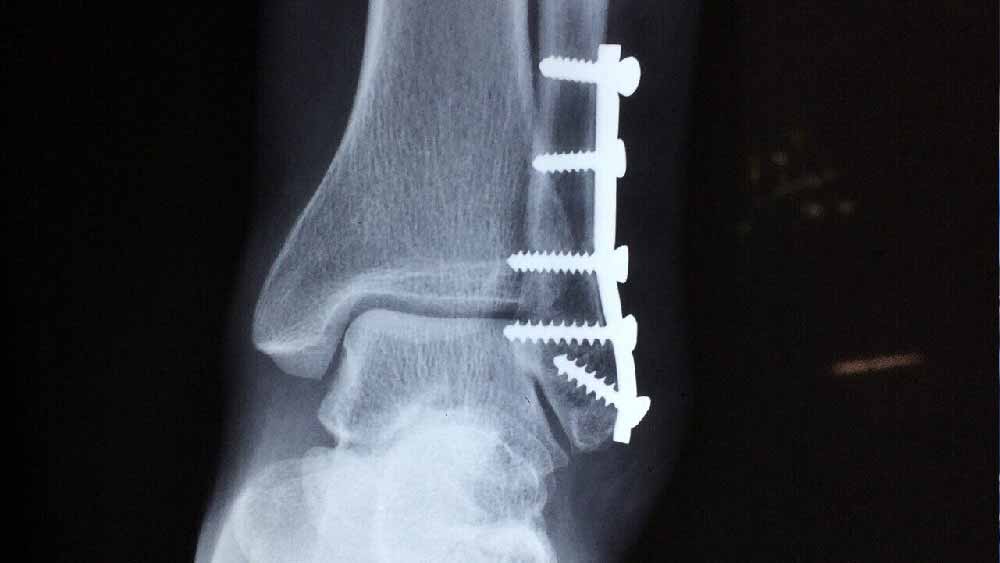

ওই কঙ্কালটি যে  মহিলার, তা  জানা গেলেও তাঁর পরিচয় সম্পর্কে তথ্য বার করতে কালঘাম ছুটে গিয়েছিল তদন্তকারীদের। আচমকাই একটি সাড়ে ৬ সেন্টিমিটারের স্ক্রু থেকে রহস্যের জট খুলে যায়!

কী ভাবে তদন্তে সাহায্য করেছিল একটি স্ক্রু? উন্মেষের কথায়, ‘‘ময়নাতদন্তের সময় ব্রাশ দিয়ে কঙ্কালের হাড়গোড় পরিষ্কার করার সময় দেখি, বাঁ-গোড়ালিতে একটি সাড়ে ৬ সেন্টিমিটারের স্ক্রু আটকানো। ওই গোড়ালিটা ভাঙা বলে মনে হচ্ছে।’’

উন্মেষ আরও বলেছিলেন, ‘‘স্টেনলেস স্টিলের এই ধরনের স্ক্রু সাধারণত ভাঙা অস্থির অস্ত্রোপচারে ব্যবহৃত হয়। এ ক্ষেত্রে ভাঙা হাড় জোড়া লাগানোর জন্য মহিলার গোড়ালিতে ওই স্ক্রু লাগানো হয়েছিল।’’

স্ক্রু-এর বিষয়টি প্রকাশ্যে আসতেই তদন্তকারীদের সামনে আচমকাই যেন একটি দরজা খুলে যায়। খুঁটিয়ে দেখার পর নজরে আসে, স্ক্রু-র গায়ে খোদাই করা উৎপাদনকারীর নাম— ‘পিটকার’। রয়েছে একটি ব্যাচ নম্বরও।

উন্মেষ বলেন, ‘‘স্ক্রু-র ব্যাচ নম্বর মিলিয়ে দেখা যায় যে ২০১৬ সালের সেপ্টেম্বরে ত্রিপুনিথুরায় ভিকেএন হাসপাতালে অস্ত্রোপচার হয়েছিল শকুন্তলার। সে সময় একটি পথদুর্ঘটনায় তাঁর গোড়ালির হাড় ভেঙে গিয়েছিল। সেই চিকিৎসায় অস্ত্রোপচারের সময় তাঁর গোড়ালিতে ওই স্ক্রু-টি লাগানো হয়েছিল।’’